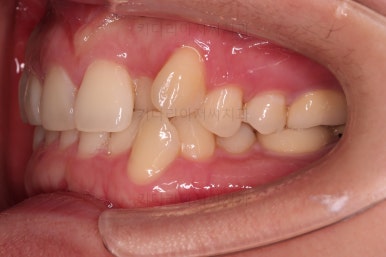

부산치과교정 키다리아저씨치과 초진 시 입안의 모습입니다.

확연히 좌우의 삐뚤어진 정도가 차이나죠.

덧니도 좌측(사진에서 보면 오른쪽) 위아래만 있는 상태고요.

좌측으로 삐뚤어져서 앞니도 좌측으로 쏠려 있는 상태였습니다.